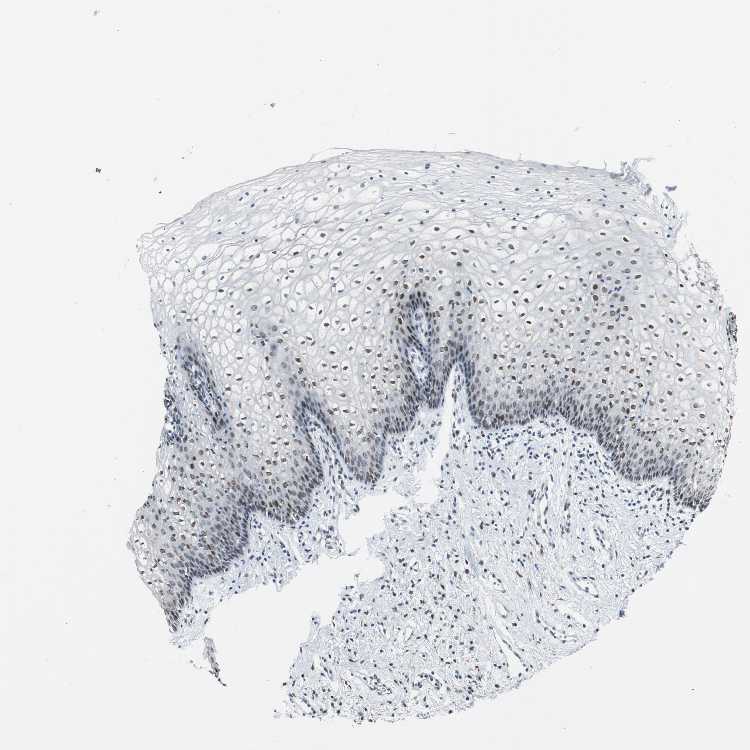

VAGINA - Antibody stainingi

Antibody staining in the annotated cell types in the current human tissue is reported as not detected, low, medium, or high, based on conventional immunohistochemistry profiling in selected tissues. This score is based on the combination of the staining intensity and fraction of stained cells.

Each image is clickable and will lead to virtual microscopy that enables deeper exploration of all samples and also displays staining intensity scores, fraction scores and subcellular localization as well as patient and tissue information for each sample.

Antibody HPA006465

Squamous epithelial cells Medium